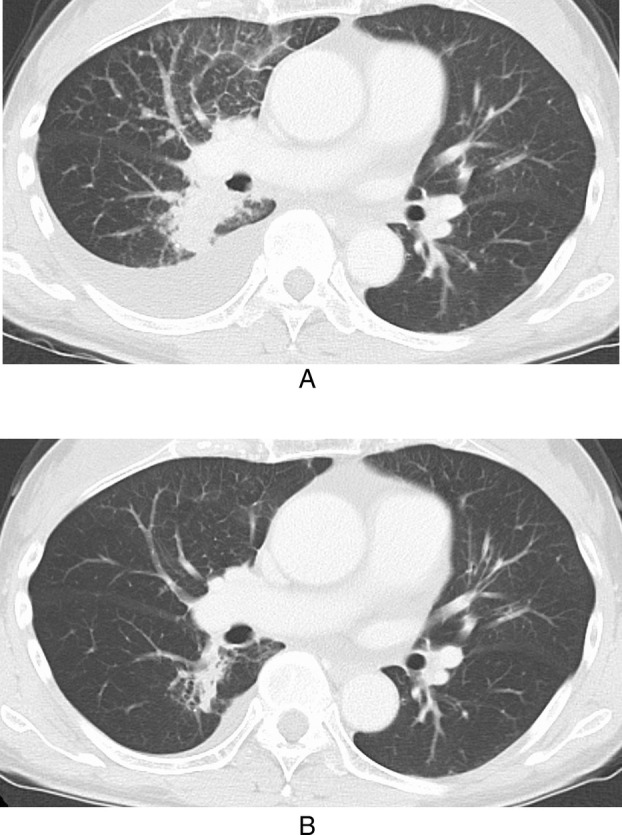

一名携带HER2 V659E突变的67岁转移性肺腺癌患者接受了曲妥珠单抗德鲁西替康(T-DXd)作为二线治疗。V659E突变是位于HER2跨膜结构域的罕见突变。在该患者中观察到的抗肿瘤效果与之前的2期试验中报道的效果相当,在2期试验中,大多数患者在激酶结构域发生突变。在这里,我们介绍详细的临床过程,并从分子生物学的角度讨论结果。

A 67-year-old patient with metastatic lung adenocarcinoma harboring a HER2 V659E mutation received trastuzumab deruxtecan (T-DXd) as second-line treatment. The V659E mutation is a rare alteration located in the transmembrane domain of HER2. The antitumor effect observed in this patient was comparable to that reported in a previous phase 2 trial, in which most patients had mutations in the kinase domain. Here, we present the detailed clinical course and discuss the findings from a molecular biological perspective.